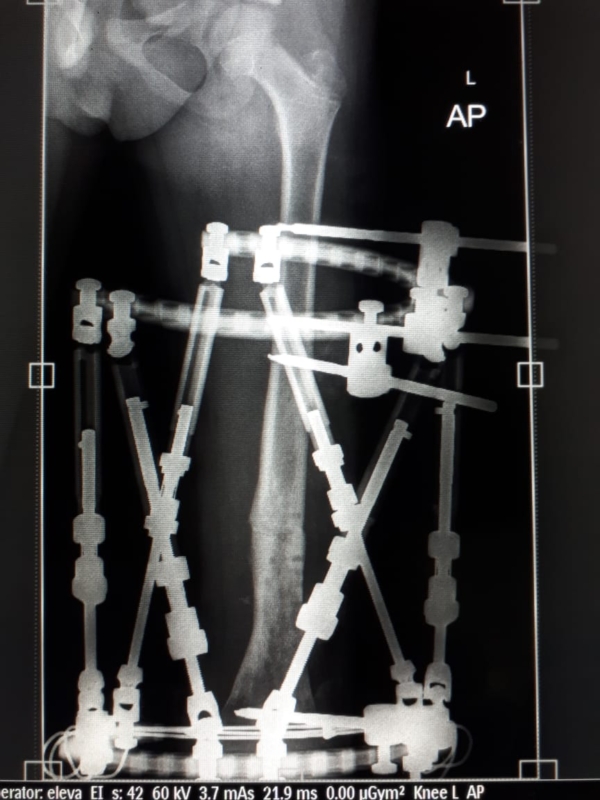

تمكن فريق طبي بمستشفى أبها للولادة والأطفال من إنهاء معاناة طفل كان يعاني من التهاب صديدي مزمن في عظمة الفخذ منذ أكثر من عام؛ وذلك عبر فريق طبي مؤلف من رئيس قسم عظام الأطفال الدكتور مهدي القرني والدكتور ظافر يوسف عباس.

وبيَّن مدير مستشفى أبها للولادة والأطفال الدكتور علي مستور تفاصيل الحالة، حيث أوضح أن هذا الطفل عانى سابقاً قبل دخوله المستشفى من أثر الالتهاب، إضافة إلى أنه قد تعرض لكسر بالفخذ ناجم عن ضعف العظم بسبب الالتهاب مما نتج عنه تشوه بالفخذ وميلان شديد مع استمرار الالتهاب.

وبعد استقبال الطفل تم تقييم حالته وأُخضِعت الحالة لعمل الفحوصات الطبية اللازمة، وأظهرت الأشعة المقطعية والمغناطيسية امتداد الالتهاب حيث تبين أنه يشمل ثلث عظمة الفخذ.

وأضاف: عقب اكتمال الإجراءات أجريت العملية بتركيب جهاز التثبيت الخارجي الحلقي (TSF) على الفخذ وإصلاح الميلان بالفخذ بشكل كامل مع إزالة القطع العظمية الملتهبة بعملية واحدة، حيث إن هذه المرة الأولى التي تستخدم فيها هذه التقنية بمستشفى أبها للولادة والأطفال.